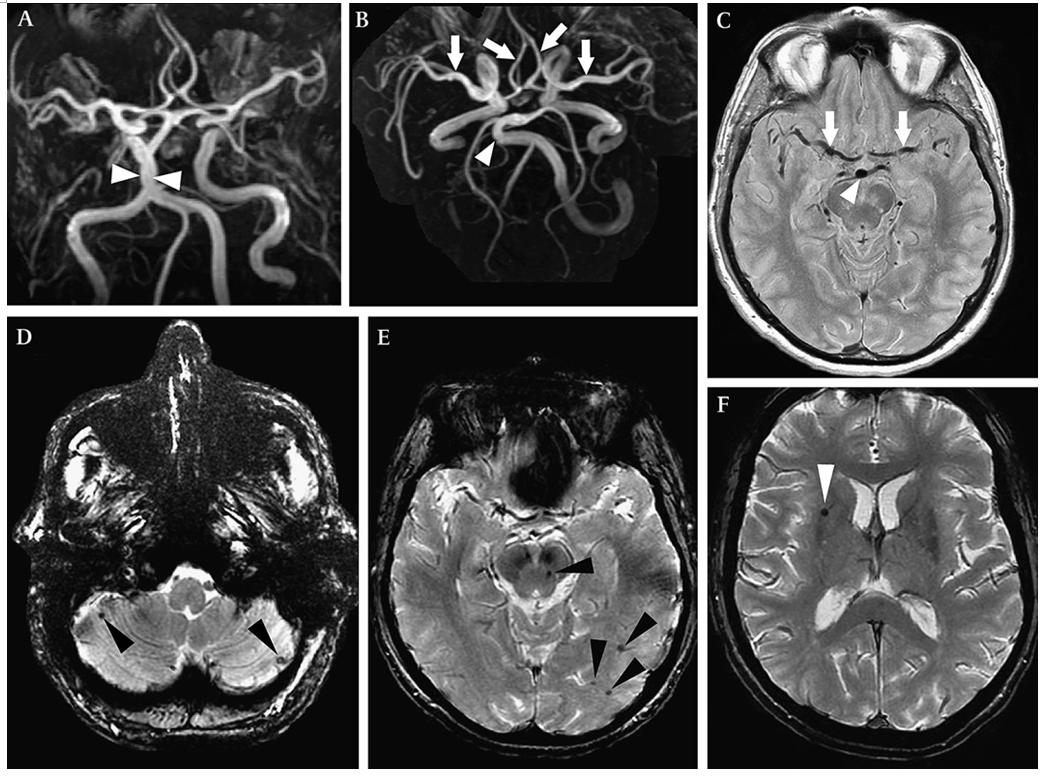

庞贝病 MRA和T2WI示基底动脉、双侧大脑前动脉和大脑中动脉扩张延长(A-C)。T2*WI示双侧小脑、脑干和大脑多发CMBs。